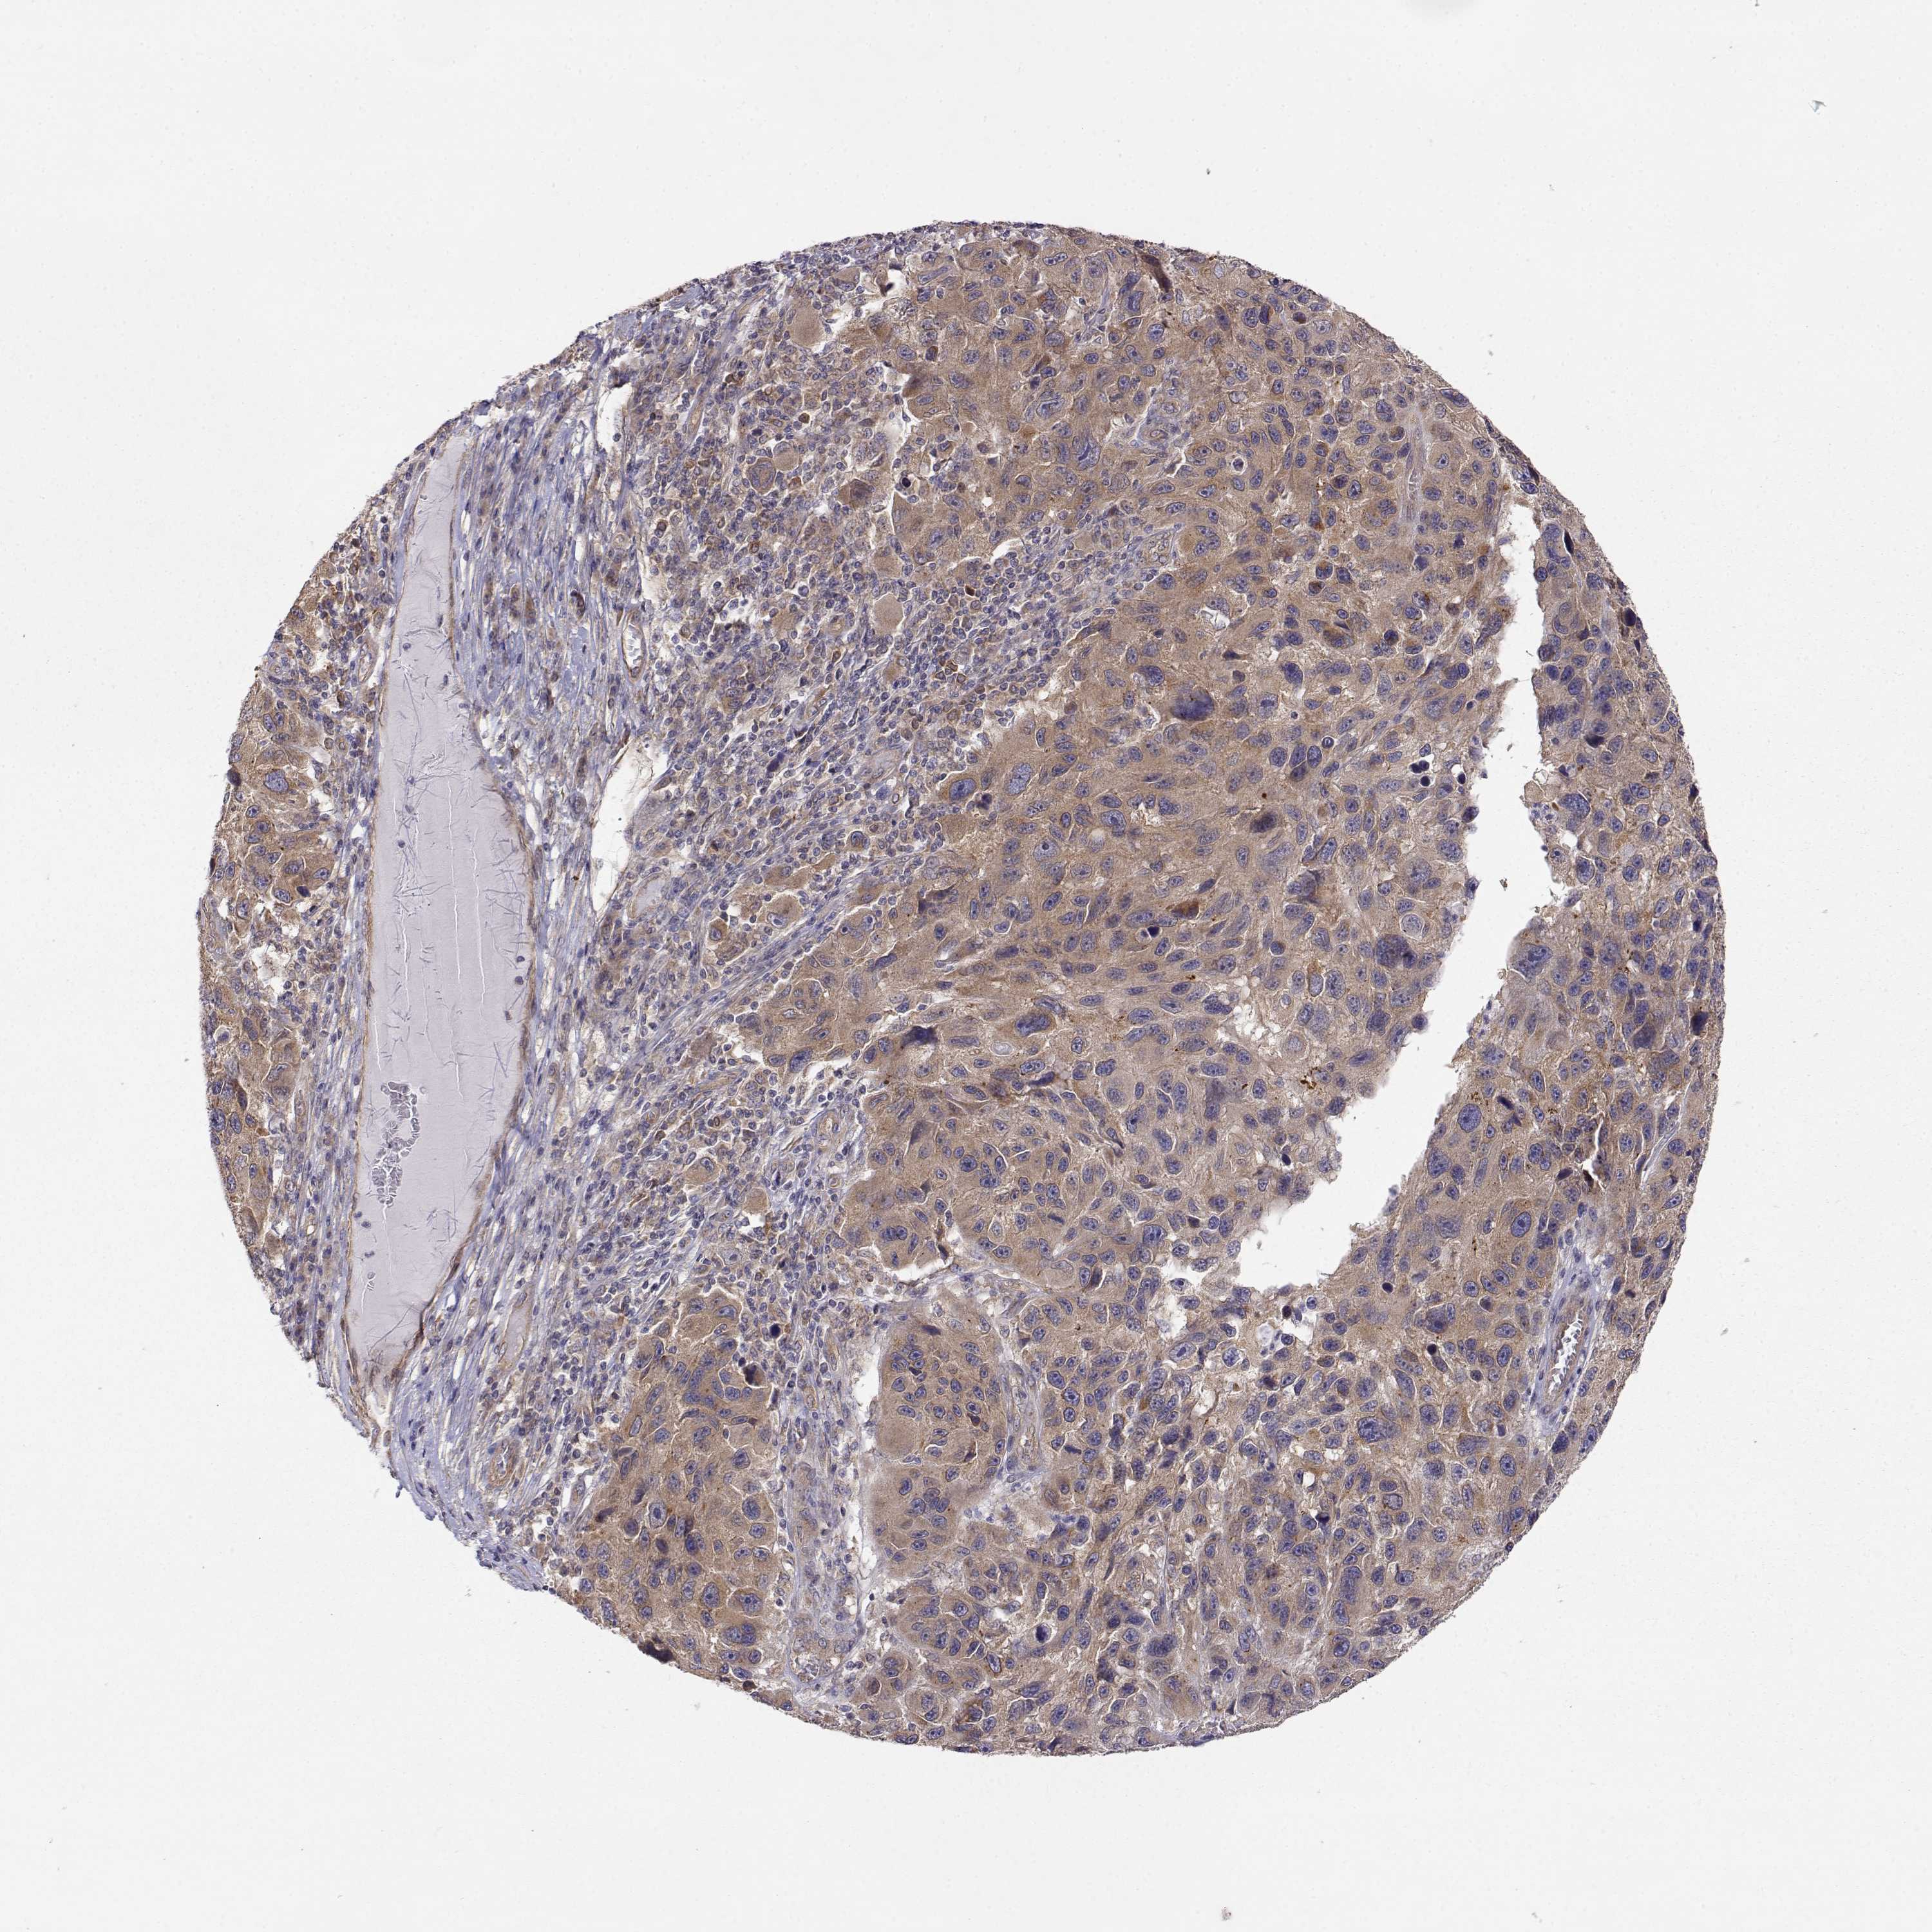

MELANOMA - Protein expressioni

A mouse-over function shows sample information and annotation data. Click on an image to view it in a full screen mode. Samples can be filtered based on level of antibody staining by selecting one or several of the following categories: high, medium, low and not detected. The assay and annotation is described here.

Note that samples used for immunohistochemistry by the Human Protein Atlas do not correspond to samples in the TCGA dataset.

Antibody stainingi

Antibody staining in the annotated cell types in the current human tissue is reported as not detected, low, medium, or high, based on conventional immunohistochemistry profiling in selected tissues. This score is based on the combination of the staining intensity and fraction of stained cells.

Each image is clickable and will lead to virtual microscopy that enables deeper exploration of all samples and also displays staining intensity scores, fraction scores and subcellular localization as well as patient and tissue information for each sample.

Antibody HPA073653

Staining

High

Medium

Low

Not detected

Intensity

Strong

Moderate

Weak

Negative

Quantity

>75%

75%-25%

<25%

None

Location

Nuclear

Cytoplasmic/membranous

Cytoplasmic/membranous,nuclear

Malignant melanoma, NOS

Malignant melanoma, Metastatic site